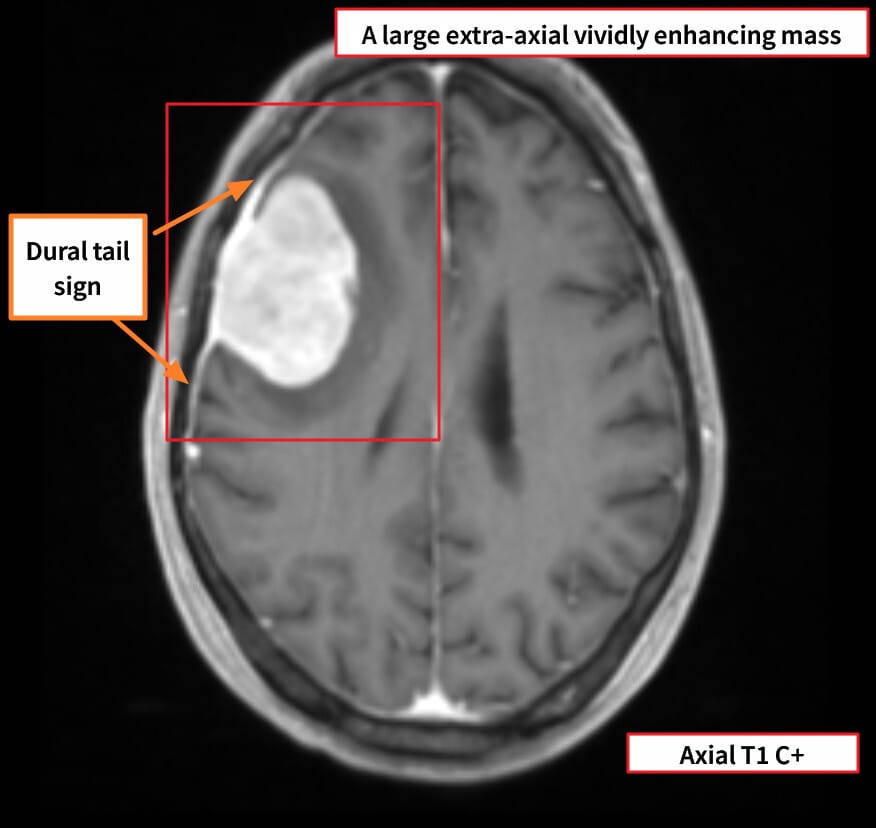

영상소견

조영 증강 MRI에서 경막에 붙어 자라는 균일한 종괴가 보입니다.

Gaillard F, Meningioma. Case study, Radiopaedia.org (Accessed on 10 May 2025) https://doi.org/10.53347/rID-44524

| Meningioma 영상소견 |

| 🔵 조영 증강 종괴 + Dural tail sign |

| 경막을 따라 꼬리처럼 조영되는 소견으로 수막종의 대표 영상 특징입니다. |

Dural Tail Sign

- Dural tail sign은 조영증강된 뇌 MRI에서 관찰되는 소견으로, 수막종(Meningioma)에서 매우 흔하게 보이는 특징입니다.

조영제를 주입한 뒤, 종양 본체에서 경막(dura mater)이 종양과 연결된 방향으로 점점 가늘어지며 조영 증강이 지속적으로 나타나며, 이 모양이 마치 “꼬리(tail)”처럼 보여서 붙은 이름입니다.